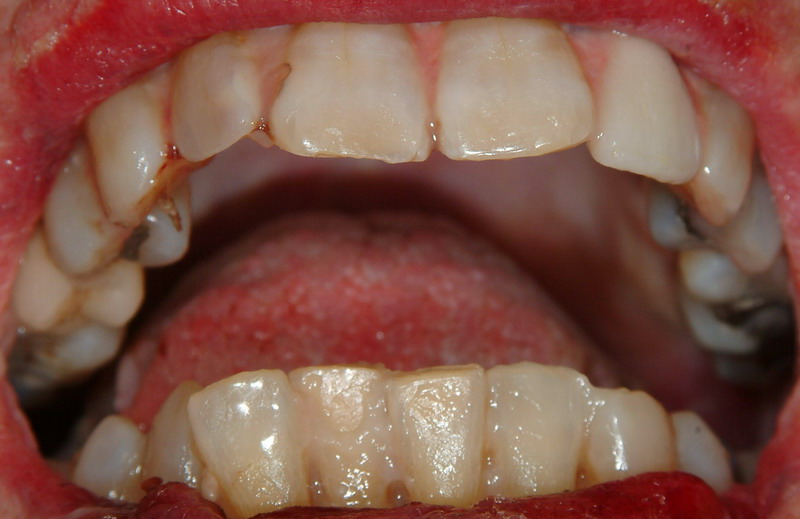

Коллеги! Решил я конкретно воспользоваться первыми плодами нашего горячо любимого ФСМ. На прошлой неделе привезли труп неизвестной женщины. После вскрытия оказалось, что скоропостижка. Ничего интересного и криминального, но остался вопрос идентификации. Случай не горящий и поэтому нас так вяло, для порядка, спросили про возраст потерпевшей. Думаю, что её скоро идентифицируют, но я решил проверить таблицы по зубам, которые FILIN выложил. Взял сразу самую "хорошую" в смысле простую и понятную таблицу для быстрой “прикидки” возраста Маскина П.А.

- к 25 годам – незначительная потертость на жевательной поверхности резцов;

- к 30 годам – небольшое обнажение дентина резцов с начальными явлениями стирания бугров жевательных зубов;

- к 35 годам – резкое обнажение дентина резцов, выраженная потертость бугров жевательных зубов;

- к 40 годам – уменьшение высоты резцов за счет стертости, обнажение дентина жевательных зубов;

- к 45 годам – выраженная стертость резцов и жевательных зубов, выпадение отдельных зубов;

- с 50 лет – постепенное кратерообразное углубление центральных отделов жевательных зубов;

- к 60 годам – значительная стертость выравнивает поверхность жевательных зубов.

Предлагаю "попробовать свои силы" в определении возраста по зубам всем желающим. Пока называть возраст, который я поставил не буду, чтобы не "оказывать давления". Я опять же весь труп видел. Но останемся при зубах.

навскидку это молодая женщина, не старше 25 лет, хотя фотографии не очень - плохо видна жевательная поверхность. Нет указания в условии на прикус

А пока, с учетом тех трудностей, которые имеются, недостаточным обзором большинства зубов, появление полоски дентина на всех резцах и начальные почвления дентина на клыках, отсутствие правой нижней 6(если правильно разглядел) - возраст примерно 31-35лет.

По фотографии 20-25.

Совсем другое дело. Изменяю возраст на 25-30л.

По таблице получается 25-30 лет.

Но вот смотрю я на пломбы. Сейчас уже такие не ставят, ставили в годах 90-х. Может тогда около 35-40 лет. Но это так от себя.

Уважаемые Мих, Filin, Vitalykk, smed!

Большое вам спасибо за участие в тестировании "зубной таблицы" г-на Маскина П.А.!

Женщину однозначно идентифицировали. Выставил этот случай на всеобщее обозрение потому, что уже на вскрытии мы все с удивлением разглядывали эти зубы. Труп типичной старушки с остеопорозом, выраженным атеросклерозом аорты, возрастной эмфиземой лёгких. Мы попожимали плечами, головами покачали, но всё объяснить в биологии нельзя. Наш шеф ещё сказал, что эта женщина видимо никогда не "обдирала" зубной налёт зубными щётками и не "травилась" зубной пастой. По внешнему виду и по сотоянию внутренних органов старушке было явно за 60 лет. Видя это несоответствие я и решил выставить этот, с моей точки зрения, интересный случай на форум. У меня есть и фотографии трупа, но выставлять их не хочу, т.к. по внешнему виду трупа можно идентифицировать личность, что противоречит правилам форума, да и здравому смыслу.

Теперь нам сообщили возраст этой старушки.

Господа эксперты! На фотографиях вы видите зубы 82 летней женщины.